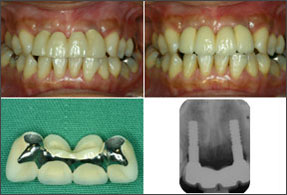

| 1ピースでの審美性の工夫(2) | ||

![]() 1999/10/04 左下6 5SM植立、2000/01/26 左下7 #568植立、2000/8/18 MBCr装着 |

![]() 2001/01/26 右上2 4LM植立、2001/10/31 右上2,右上1,左上1,左上2 MBCr着 |

![]() 2006/08/23 右上2 植立5Y1M後、左下6 植立7Y11M後、左下7 植立6Y7M後、前歯、臼歯共に審美性を保っている。右上2は、右上1,左上1,2などの天然歯と何ら遜色はない。 |